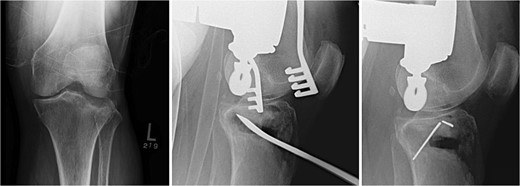

A 5 × 170 mm Schanz pin is placed percutaneously in the distal tibial shaft after bicortically predrilling with a 3.5 mm drill bit with irrigation. Another 5 × 170 mm Schanz pin is placed parallel to the joint at the level of the lateral epicondyle after bicortically predrilling with a 3.5 mm drill. A universal distractor is placed to enhance joint distraction. A submeniscal arthrotomy is performed parallel to the lateral meniscus to visualize the joint and to inspect the lateral meniscus for tears. Cartilage injury and subchondral bone depression are evaluated as well. The lateral plateau is disimpacted and elevated up using an osteotome deep to the depressed articular surface. Several K-wires are placed lateral to medial through the medial cortex to temporarily hold the alignment of the joint line when it is elevated. The K-wires are pulled out medially until they are flush with the cortex of the lateral plateau. Cancellous allograft is placed under the subchondral bone to reinforce the usually thin articular surface (Fig. 1).

Fracture reduction, articular reduction, posterior slope restoration, and temporary fixation with K-wire.